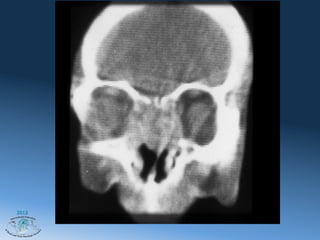

Хондросаркома

C T Scan- Coronal View

режим мягких тканей и костный режим

Хондросаркома C T Scan- Coronal View режим мягких тканей и костный режим 2012